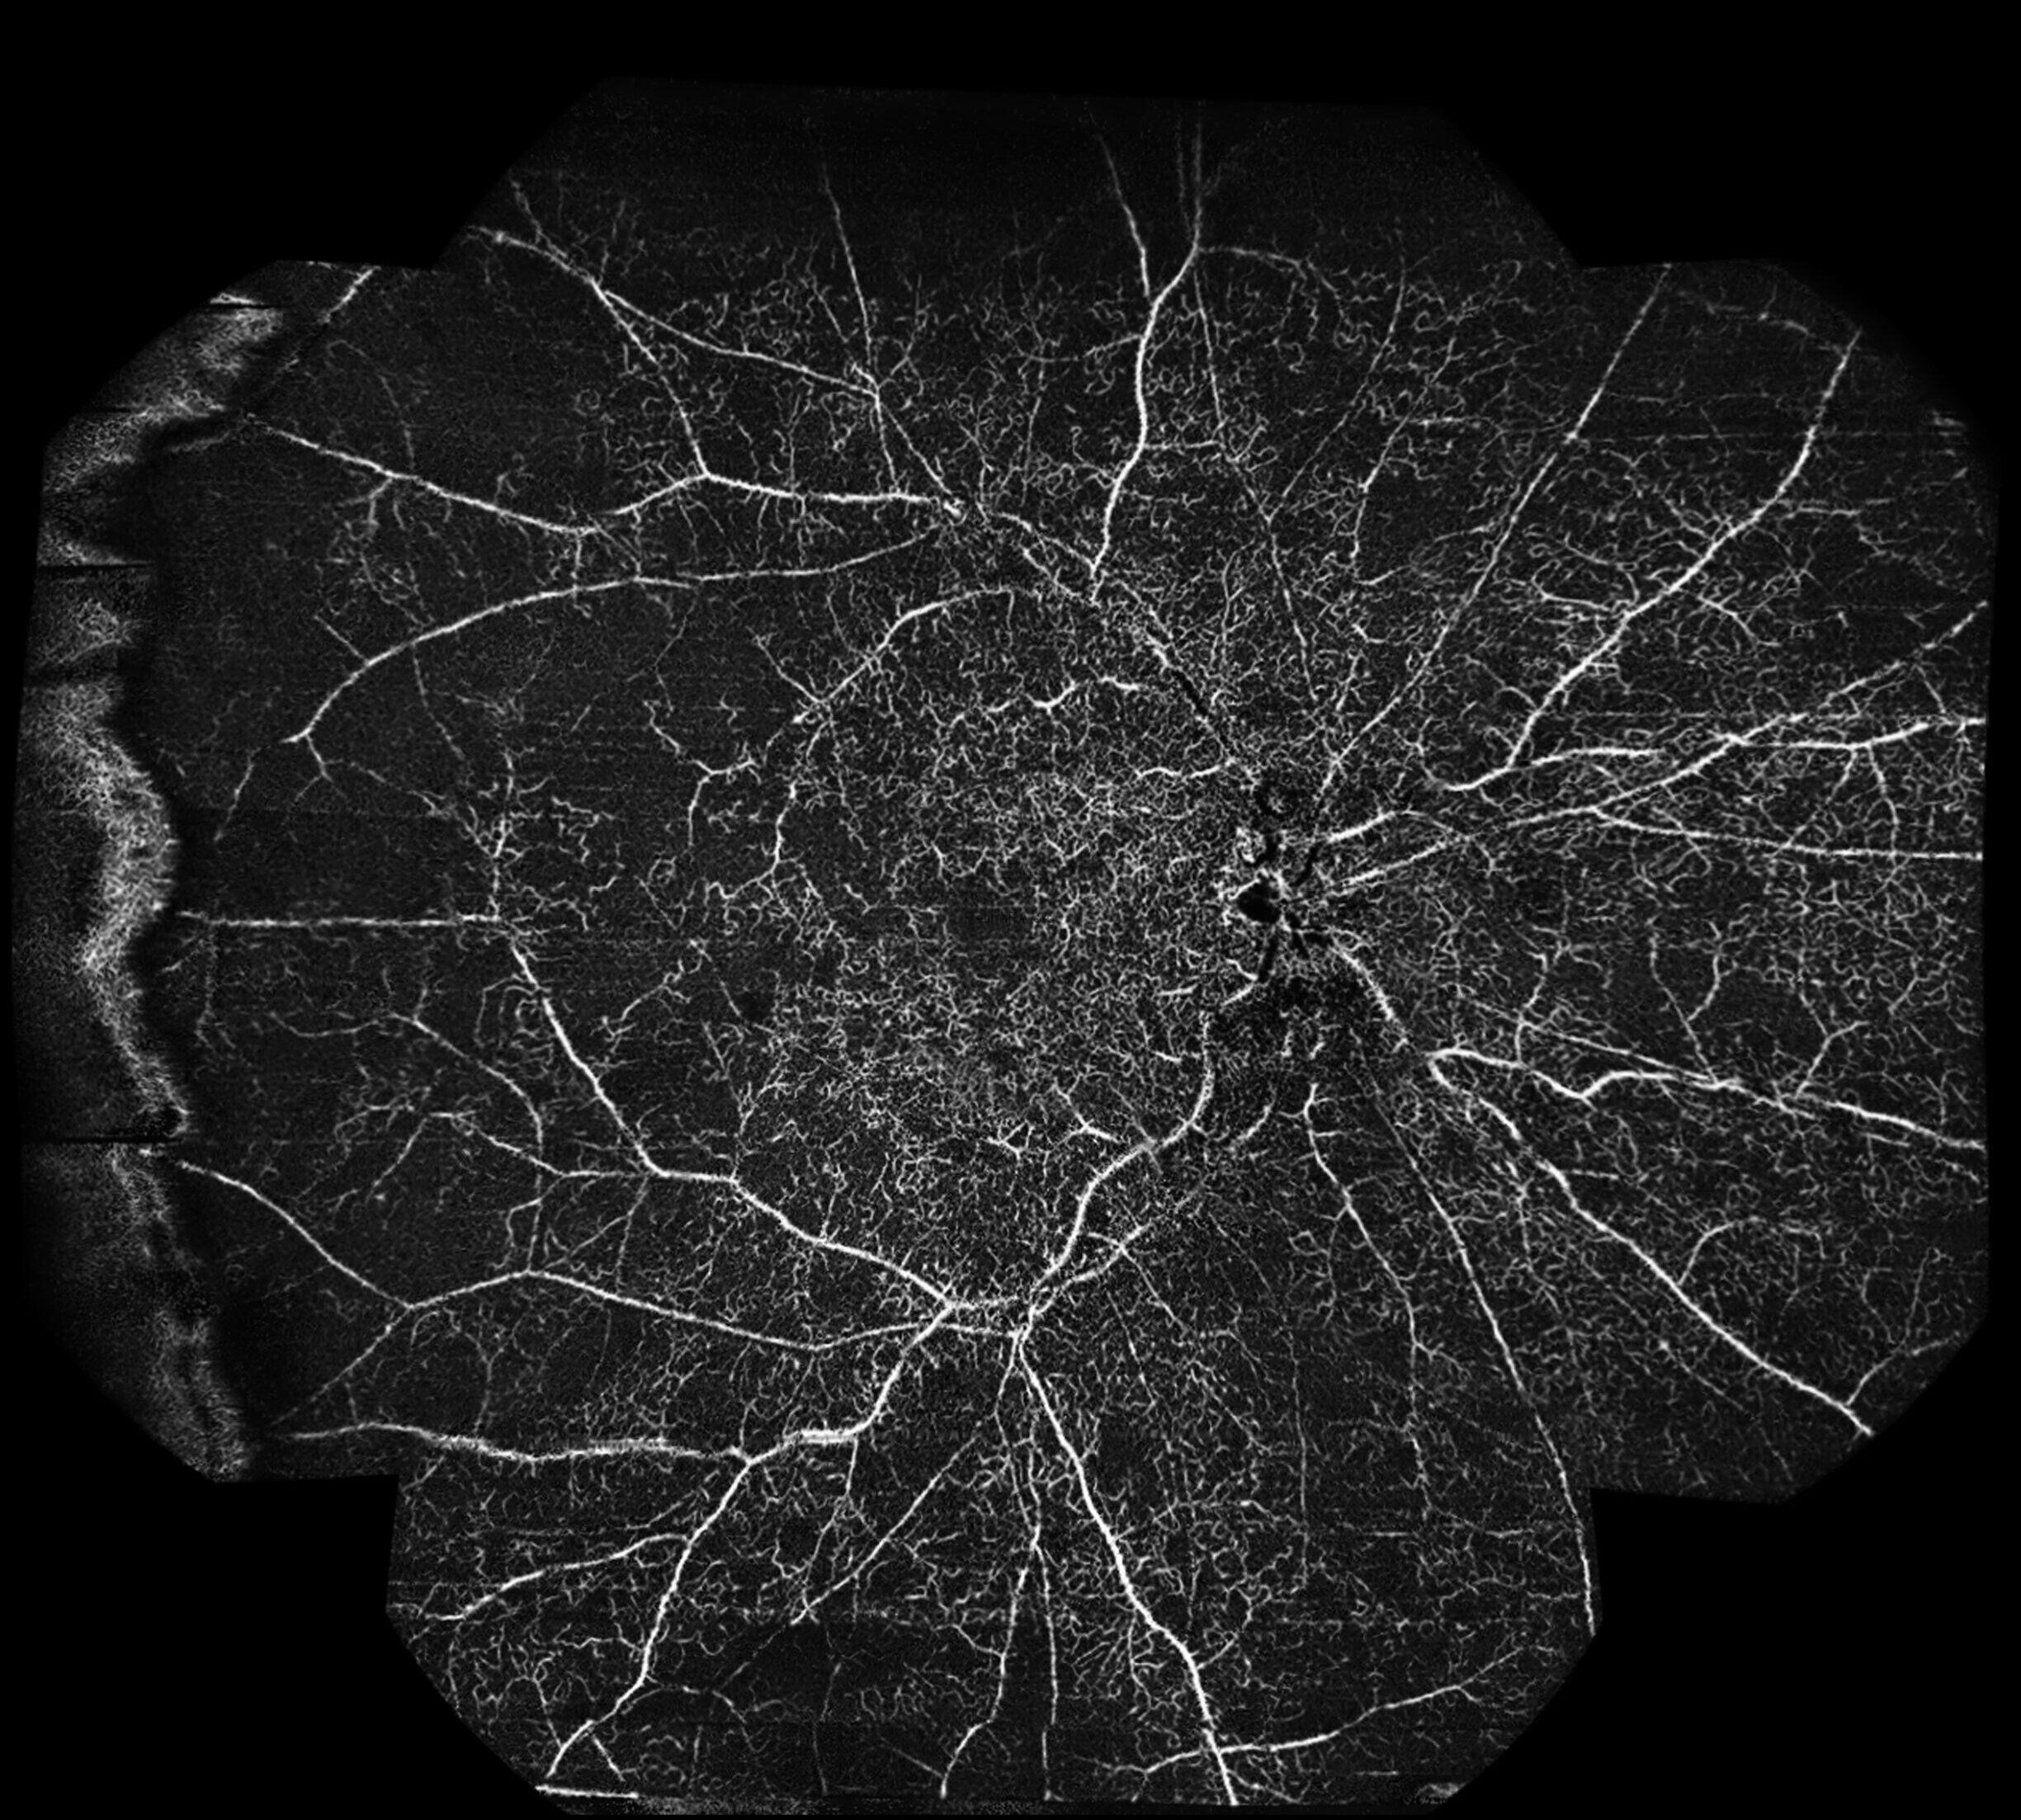

The ultra-widefield OCTA image provides an extended view of the retinal vasculature beyond the posterior pole. In the post-treatment scan, the superficial vascular plexus (top image) demonstrates improved perfusion centrally, although extensive areas of capillary nonperfusion are still evident in the midperiphery and periphery. The deep plexus (second one) reveals more pronounced dropout, with diffuse hypoperfused zones reflecting irreversible ischemic damage. Overall, the ultra-widefield OCTA highlights the persistent peripheral ischemia in spite of treatment, underlining the value of widefield imaging in assessing the full extent of vascular compromise in central retinal vein occlusion.